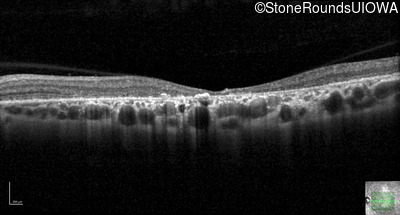

All three of the cardinal ophthalmic features of Mendelian macular dystrophies are present in this patient. The most striking features of the fundus exam are the numerous yellow flecks at the level of the RPE. Flecks are most commonly seen in AR Stargardt disease and pattern dystrophy although they may be seen in some of the rarer Mendelian maculopathies as well. The visual acuity in patients with AR Stargardt disease is often "worse than the fundus looks" while the acuity in pattern dystrophy is often quite good despite extensive flecks. The pedigree of this patient is compatible with ABCA4-associated Stargardt disease and the better than expected acuity is attributable to foveal sparing (see below). The onset of reduced acuity at age 10 is much more characteristic of ABCA4 disease than pattern dystrophy. Another feature present in this patient that is very frequently seen in Stargardt disease is peripapillary sparing. However, this sign can be seen in pattern dystrophy as well. When central atrophy is present in ABCA4-associated Stargardt disease it often somewhat shiny (which is uncommon with the geographic atrophy of pattern dystrophy or age-related macular degeneration). Some patients with ABCA4-associated Stargardt disease can have some preservation of the fovea giving a zonal "bullseye" appearance to the center of the macula. Sometimes this preservation is associated with preserved acuity as in this case. The outer nuclear layer (ONL) is much thinner than normal on OCT, indicative of photoreceptor loss. This is associated with a thinning of the ellipsoid zone which is usually many times brighter and thicker than the external limiting membrane (ELM). These two lines are essentially equal in intensity in this patient. The foveal sparing is seen on OCT only as a small bit of retinal convexity in the center of the atrophy coupled with a small bit of residual RPE flanked by bare Bruch's membrane. The presence of a robust I2e isopter on Goldmann perimetry places this patient in the least severe half of all Stargardt patients (see Schindler, et al., 2010). Most patients with ABCA4-associated disease are somewhat myopic as is this patient. Stargardt patients also tend to perform very poorly on pseudoisochromatic plates, even when their acuity is still fairly good as it is here.